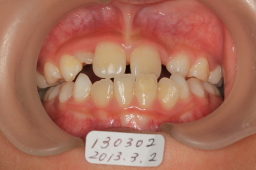

2013年03月02日 初診

前歯反対咬合

噛み合わせの高さをあげて、切歯斜面板で交叉咬合の改善を図る。骨格性の反対咬合